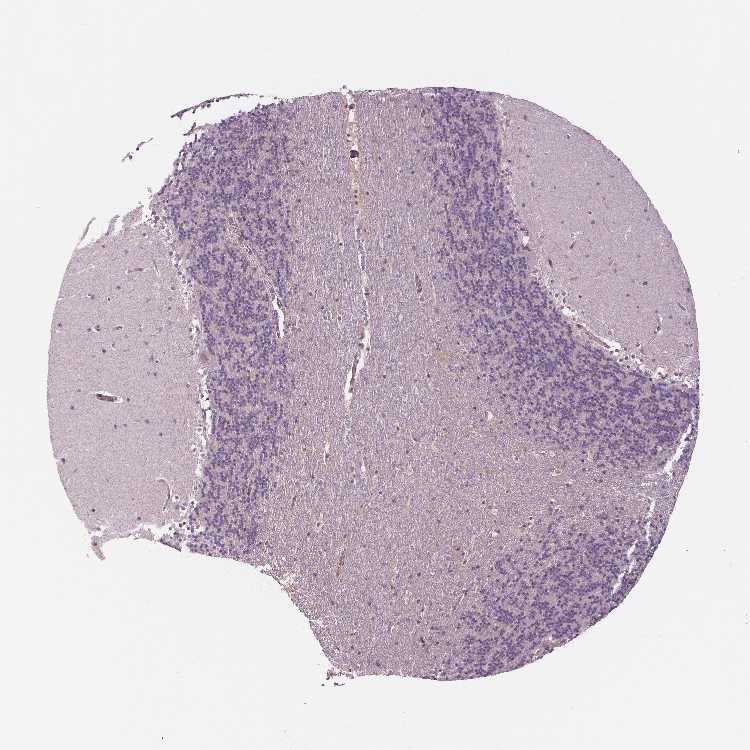

CEREBELLUM - Antibody stainingi

Antibody staining in the annotated cell types in the current human tissue is reported as not detected, low, medium, or high, based on conventional immunohistochemistry profiling in selected tissues. This score is based on the combination of the staining intensity and fraction of stained cells.

Each image is clickable and will lead to virtual microscopy that enables deeper exploration of all samples and also displays staining intensity scores, fraction scores and subcellular localization as well as patient and tissue information for each sample.

Antibody HPA001671Antibody HPA058603Antibody CAB003859Antibody CAB068241Antibody CAB068242

Purkinje cells Not detectedNot detectedMediumNot detected-

Cells in granular layer Not detectedNot detectedNot detectedNot detected-

Cells in molecular layer Not detectedNot detectedNot detectedNot detected-